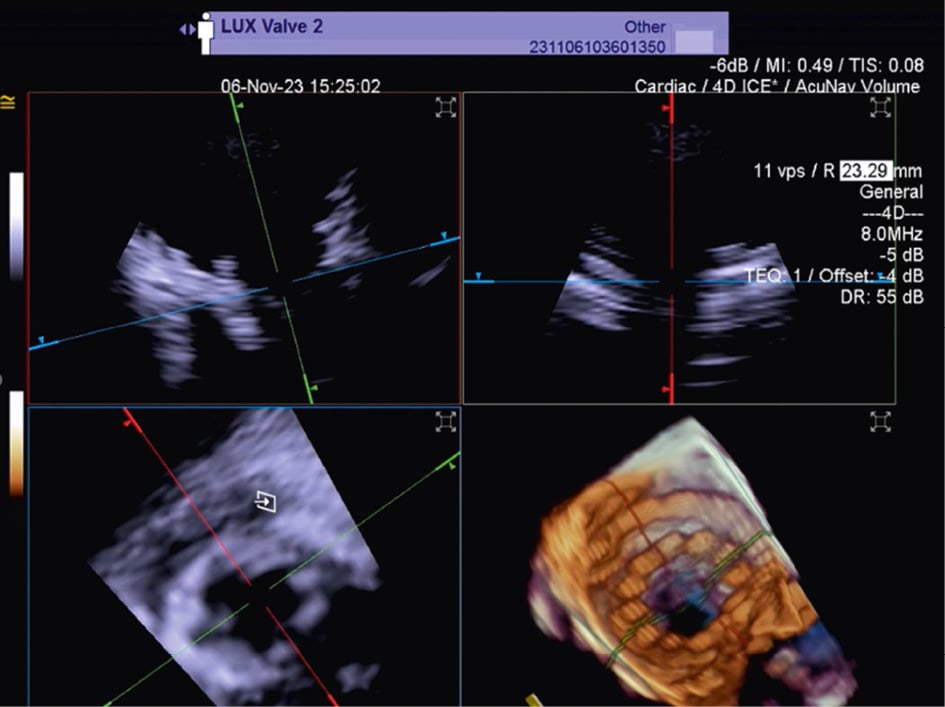

Transcatheter tricuspid valve replacement

TTVR is a new technology used for tricuspid regurgitation (TR) treatment in patients not eligible for other percutaneous approaches23. The suitability for this treatment mainly depends on the annular dimensions, and unlike other treatment approaches, the imaging quality requirements are not very strict24. Three-dimensional ICE plays a crucial role in guiding the TTVR procedure, especially when TOE imaging is technically challenging. There are currently some cases described in the literature in which TTVR procedures are performed using combined 3D TOE-ICE imaging. Furthermore, there are only a limited number of centres with experience in ICE-guided TTVR24, but considering the advantages of image quality, it could become the standard in the coming years. Typically, the ICE probe is inserted via transfemoral or transjugular access and positioned in the middle of the RA. By placing the 3D ICE probe directly in the RA, the problem of acoustic interference can be overcome. Furthermore, this position allows for stable visualisation of the TV and enables the acquisition of a 3D MPR by placing the region of interest over the TV annulus, creating a 3D en face view. The leaflet capture and the valve implantation can be guided stepwise with 3D MPR25. A dedicated echocardiographer is essential to create and optimise the imaging modalities (TOE and ICE). In fact, considering that intraprocedural echocardiographic guidance is essential for procedural success, the interventional imager plays a crucial role in guiding the implantation of the device. Figure 5, Figure 6 and Moving image 8 show a Cardiovalve case (Venus Medtech) and a LuX-Valve case (Jenscare Scientific).

Figure 5. 3D MPR ICE imaging showing Cardiovalve device opening at the level of the tricuspid annulus. 3D: three-dimensional; ICE: intracardiac echocardiography; MPR: multiplanar reconstruction